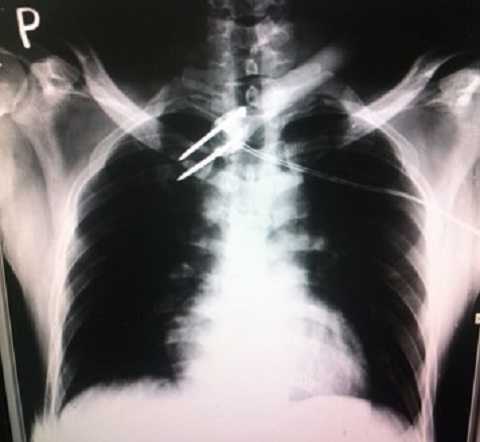

Ngày 14/8, bác sĩ Trương Thế Hiệp - Phó khoa cấp cứu Bệnh viện Chợ Rẫy TPHCM - cho biết, lúc 3h45 sáng cùng ngày, bệnh viện tiếp nhận một dân quân tự vệ từ tỉnh Long An chuyển lên trong tình trạng bị một mũi tên (có dây điện) găm sâu vào ngực.

Trả lời phóng viên, anh Thắng nói mũi tên bắn anh là loại vũ khí mà những kẻ trộm chó thường sử dụng để bắn chó. Sau khi bị dính mũi tên, anh Thắng cho biết, anh đã bị điện giật và ngã xuống đất. Tuy không bất tỉnh nhưng anh không thể cử động được. Tổ dân quân tự vệ lúc đó có 4 người và chỉ được trang bị gậy.